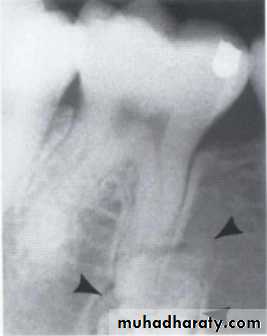

Benign cyst: lack of peripheral cortex(retention

pseudo cyst) indicates that it originated in thesinus (non-odontogenic origin).